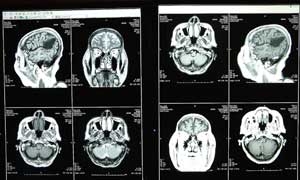

ทีมนักวิจัยมหาวิทยาลัยออกซ์ฟอร์ดชื่อดังของอังกฤษ ได้ใช้เครื่องตรวจสแกนสมองเป็นเครื่องมือในการตรวจศึกษาพบว่า สมองของคนที่กำลังมีความเจ็บปวด จะต่างกับสมองของคนปกติอย่างเห็นได้ชัด

หัวหน้าคณะนักวิจัยศาสตราจารย์ไอรีน เทรซี กล่าวว่า ความเจ็บปวดดูเหมือนจะทำให้เลือดไปเลี้ยงสมองบางส่วนมากขึ้น สุดแต่ความเจ็บปวดมากน้อย เราจะสามารถใช้เครื่องตรวจสแกนสมองวัดปฏิกิริยาที่เกิดขึ้นในสมองนั้นได้

นักวิทยาศาสตร์พบว่าสมองมีสิ่งที่เรียกว่า "เบ้าความเจ็บปวด" โดยมันจะส่งความรู้สึกนั้นไปกระตุ้นบริเวณสมองส่วนต่างๆ ถึงสิบกว่าส่วน ซึ่งต่างจากประสาทสัมผัสอื่น อย่างเช่น การเห็น หรือได้ยิน ซึ่งจะไปกระตุ้นสมองเพียงส่วนเดียวเพื่อให้ตีความ.